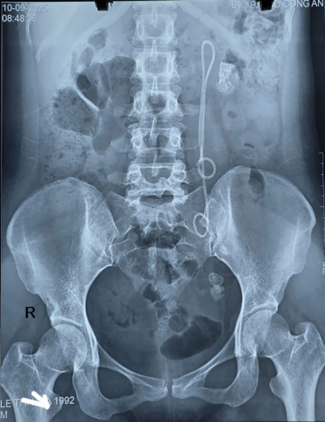

Qua thăm khám lâm sàng và cận lâm sàng, bệnh nhân được chẩn đoán: Sỏi thận trái, sỏi niệu quản trái đoạn 1/3 dưới, còn Sonde JJ trái đặt 15 năm chưa rút.

Hình ảnh XQ của bệnh nhân. Ảnh: Bệnh viện 19-8

Trường hợp này, do Sonde JJ tồn tại tới 15 năm, bệnh nhân xuất hiện sỏi to ở nhiều vị trí, Sonde bám sỏi và di chuyển bất thường, khiến quá trình điều trị phức tạp và tiềm ẩn nhiều nguy cơ.